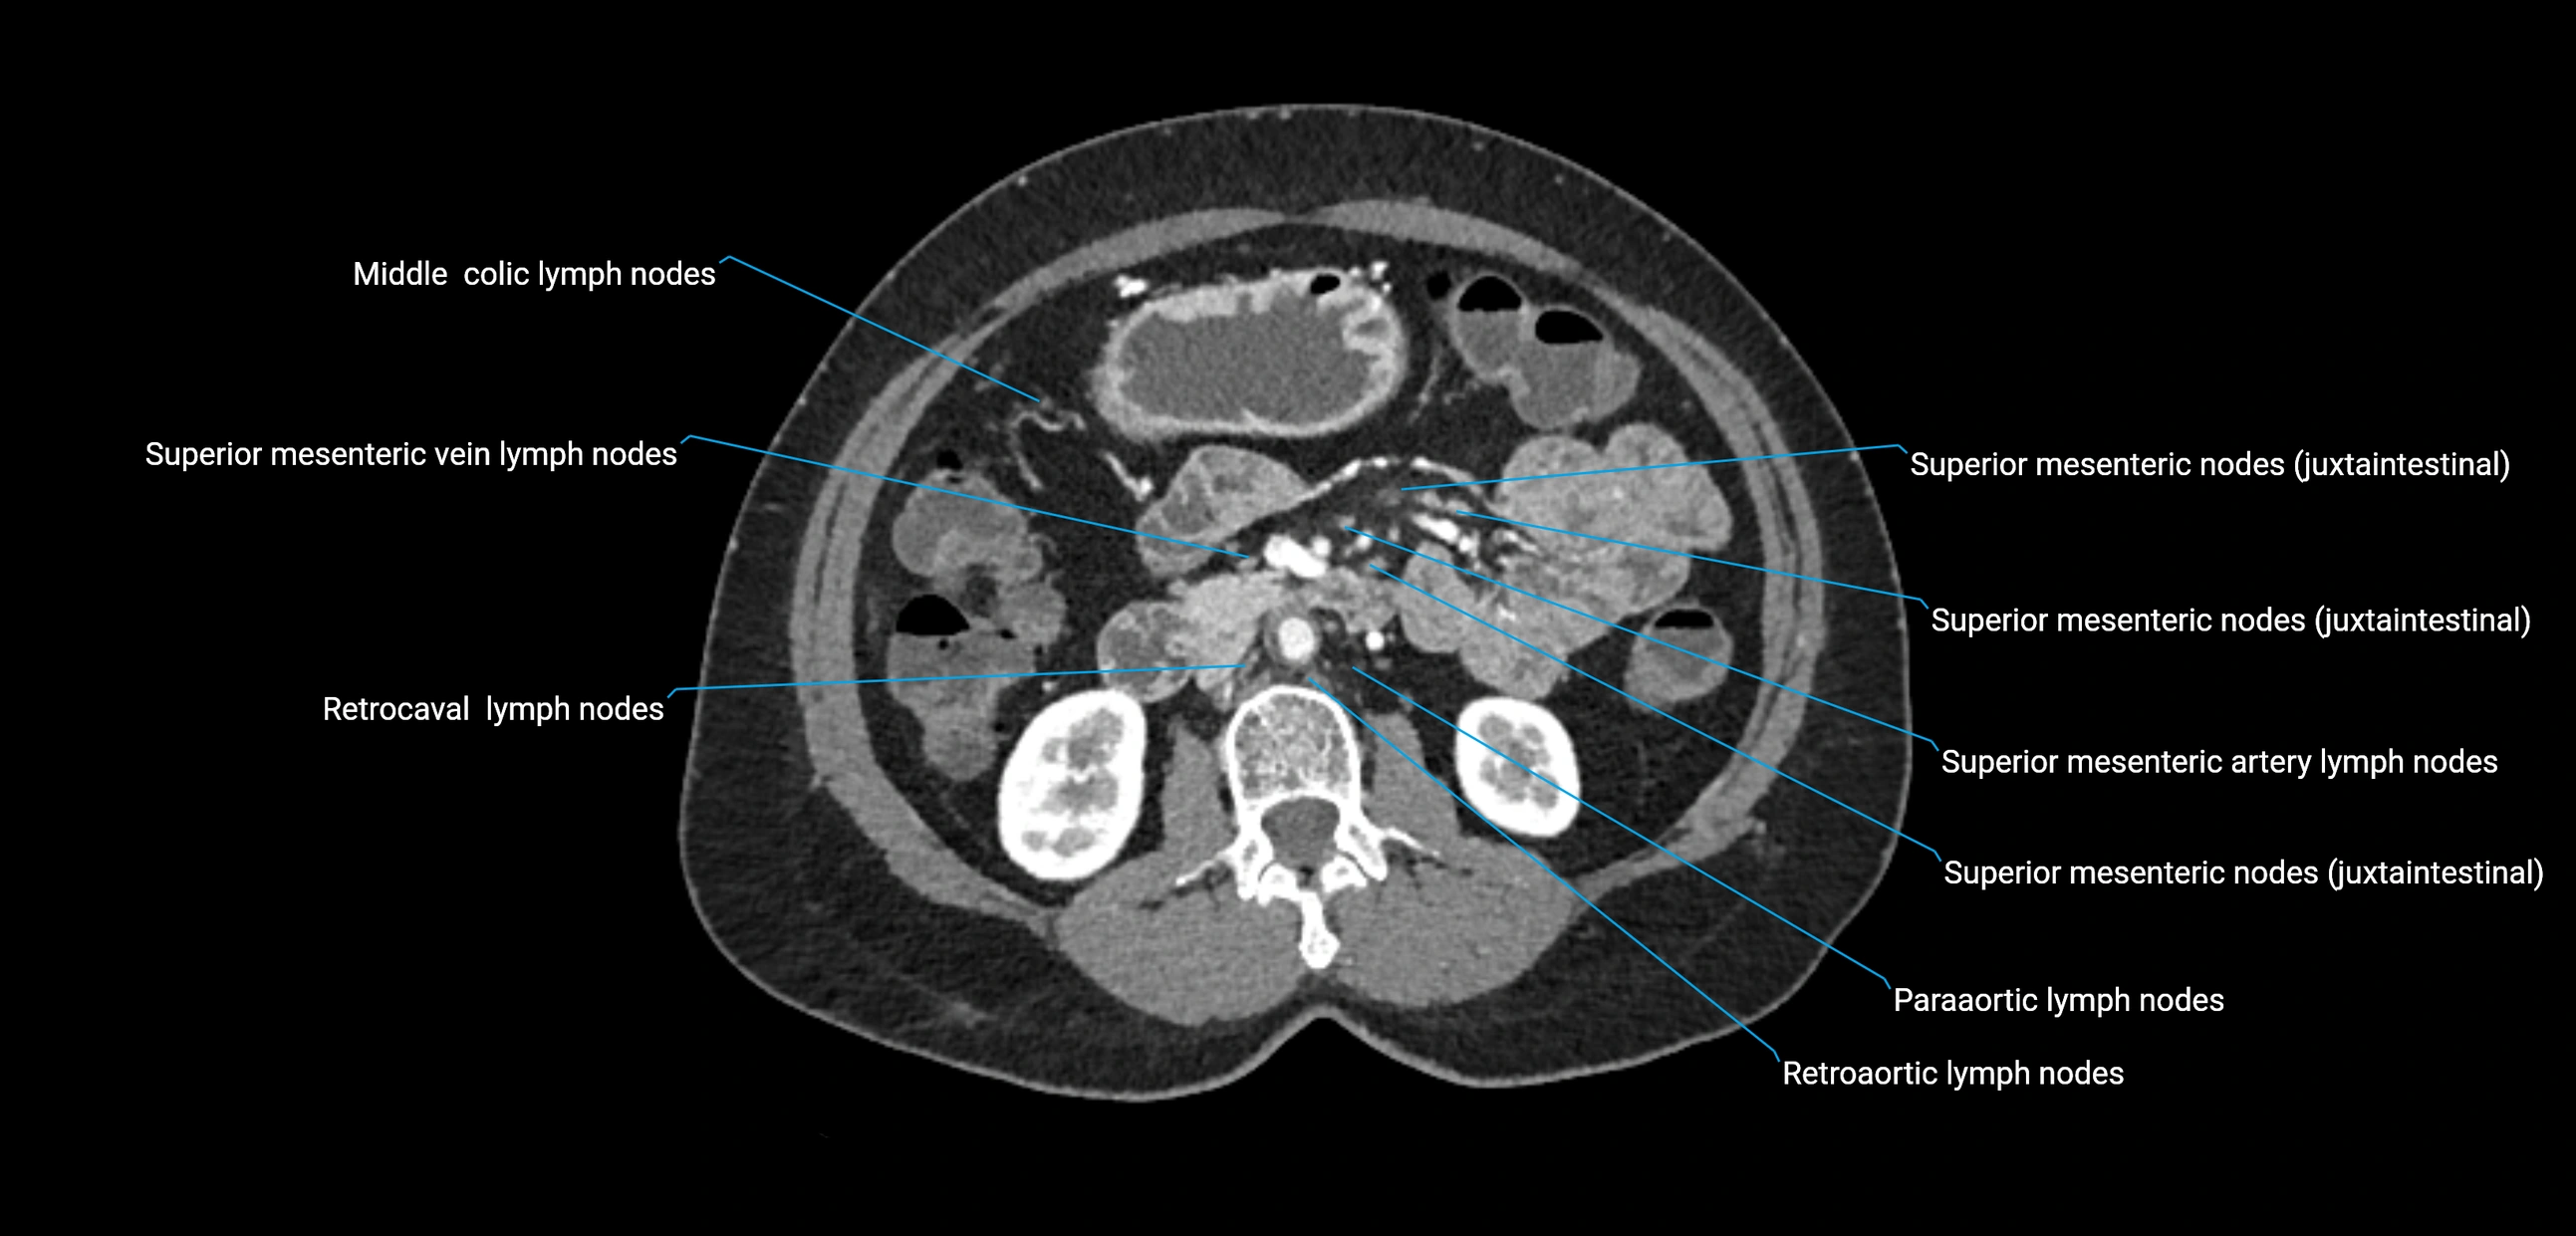

CT image

image